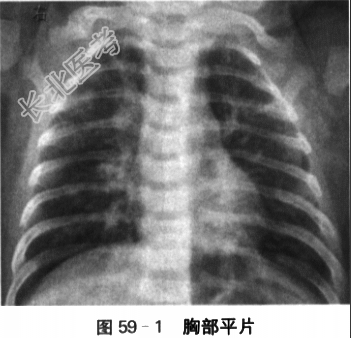

患儿,男,10月,因"咳嗽5d伴喘息2d"入院。患儿5d前因接触"感冒"家长,出现流涕、鼻塞、咳嗽。流涕、鼻塞好转,咳嗽逐渐加重,伴有痰鸣。2d前,咳嗽时伴有喘息,以活动及清晨咳嗽阵发性加剧时更为明显。病初2d有发热,38℃左右,未予以处理,自行退热。病程中无明显呕吐、腹痛、腹泻,无明显气促、呼吸困难,无尿时哭吵,无惊厥等。精神、胃纳可,睡眠欠佳。曾予以口服抗生素、止咳治疗,疗效不佳。患儿为G₁P₁,孕40周自然分娩。BW3250g。出生Apgar评分10分。否认母亲孕期感染或服药史,及围产期窒息缺氧病史。否认家族传染病和遗传病史。生后母乳喂养,2月开始面部有湿疹,局部用药已明显好转。6月能坐,9月萌牙2颗。体格检查:T37.6℃,P140次/min,R40次/min,BP78mmHg/46mmHg,Wt9.0kg。神清,精神可,巩膜无黄染,皮肤无瘀点、瘀斑,前囟1.5cm×1.5cm,平,颈部软。气管居中,无明显鼻翼煽动、吸凹征、口唇发绀。HR140次/min,律齐。两肺音粗,可及痰鸣音和哮鸣音。腹部平软,肝脏肋下1.5cm,质地软,脾未及。双下肢无水肿。SaO₂94%。实验室检查:(1)血常规检查:Hb118g/L,WBC6.8×10⁹/L,N45.1%,LY48.1%,PLT167×10⁹/L,CRP10mg/L。(2)病原学检查:呼吸道合胞病毒(+),呼吸道流感、副流感、腺病毒、军团菌等均为阴性;MP-IgM(-)、MP-IgG(-),CP-IgM(-);RSV(+);呼吸道分泌物细菌培养(-)。 (3)胸部X线检查:两肺纹理增多、紊乱,内中带见少许点片状影,左下肺轻度气肿改变(见图59-1)。(4)肺功能检查:患儿潮气呼吸功能异常,存在中度阻塞性病变。